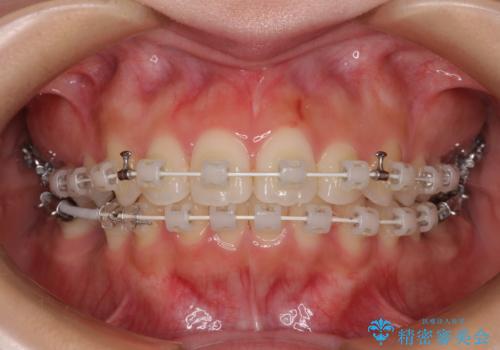

- 矯正装置

- 審美装置

- 治療期間

- 1年9ヶ月

上顎前歯の突出感は、上顎全体が前方に位置していることが原因であったため、補助装置により上顎全体を後方に移動させることとしました。

後方移動と同時上下歯列をワイヤー装置にて整え、奥歯の欠損部には矯正治療の途中でインプランを埋入していくこととしました。